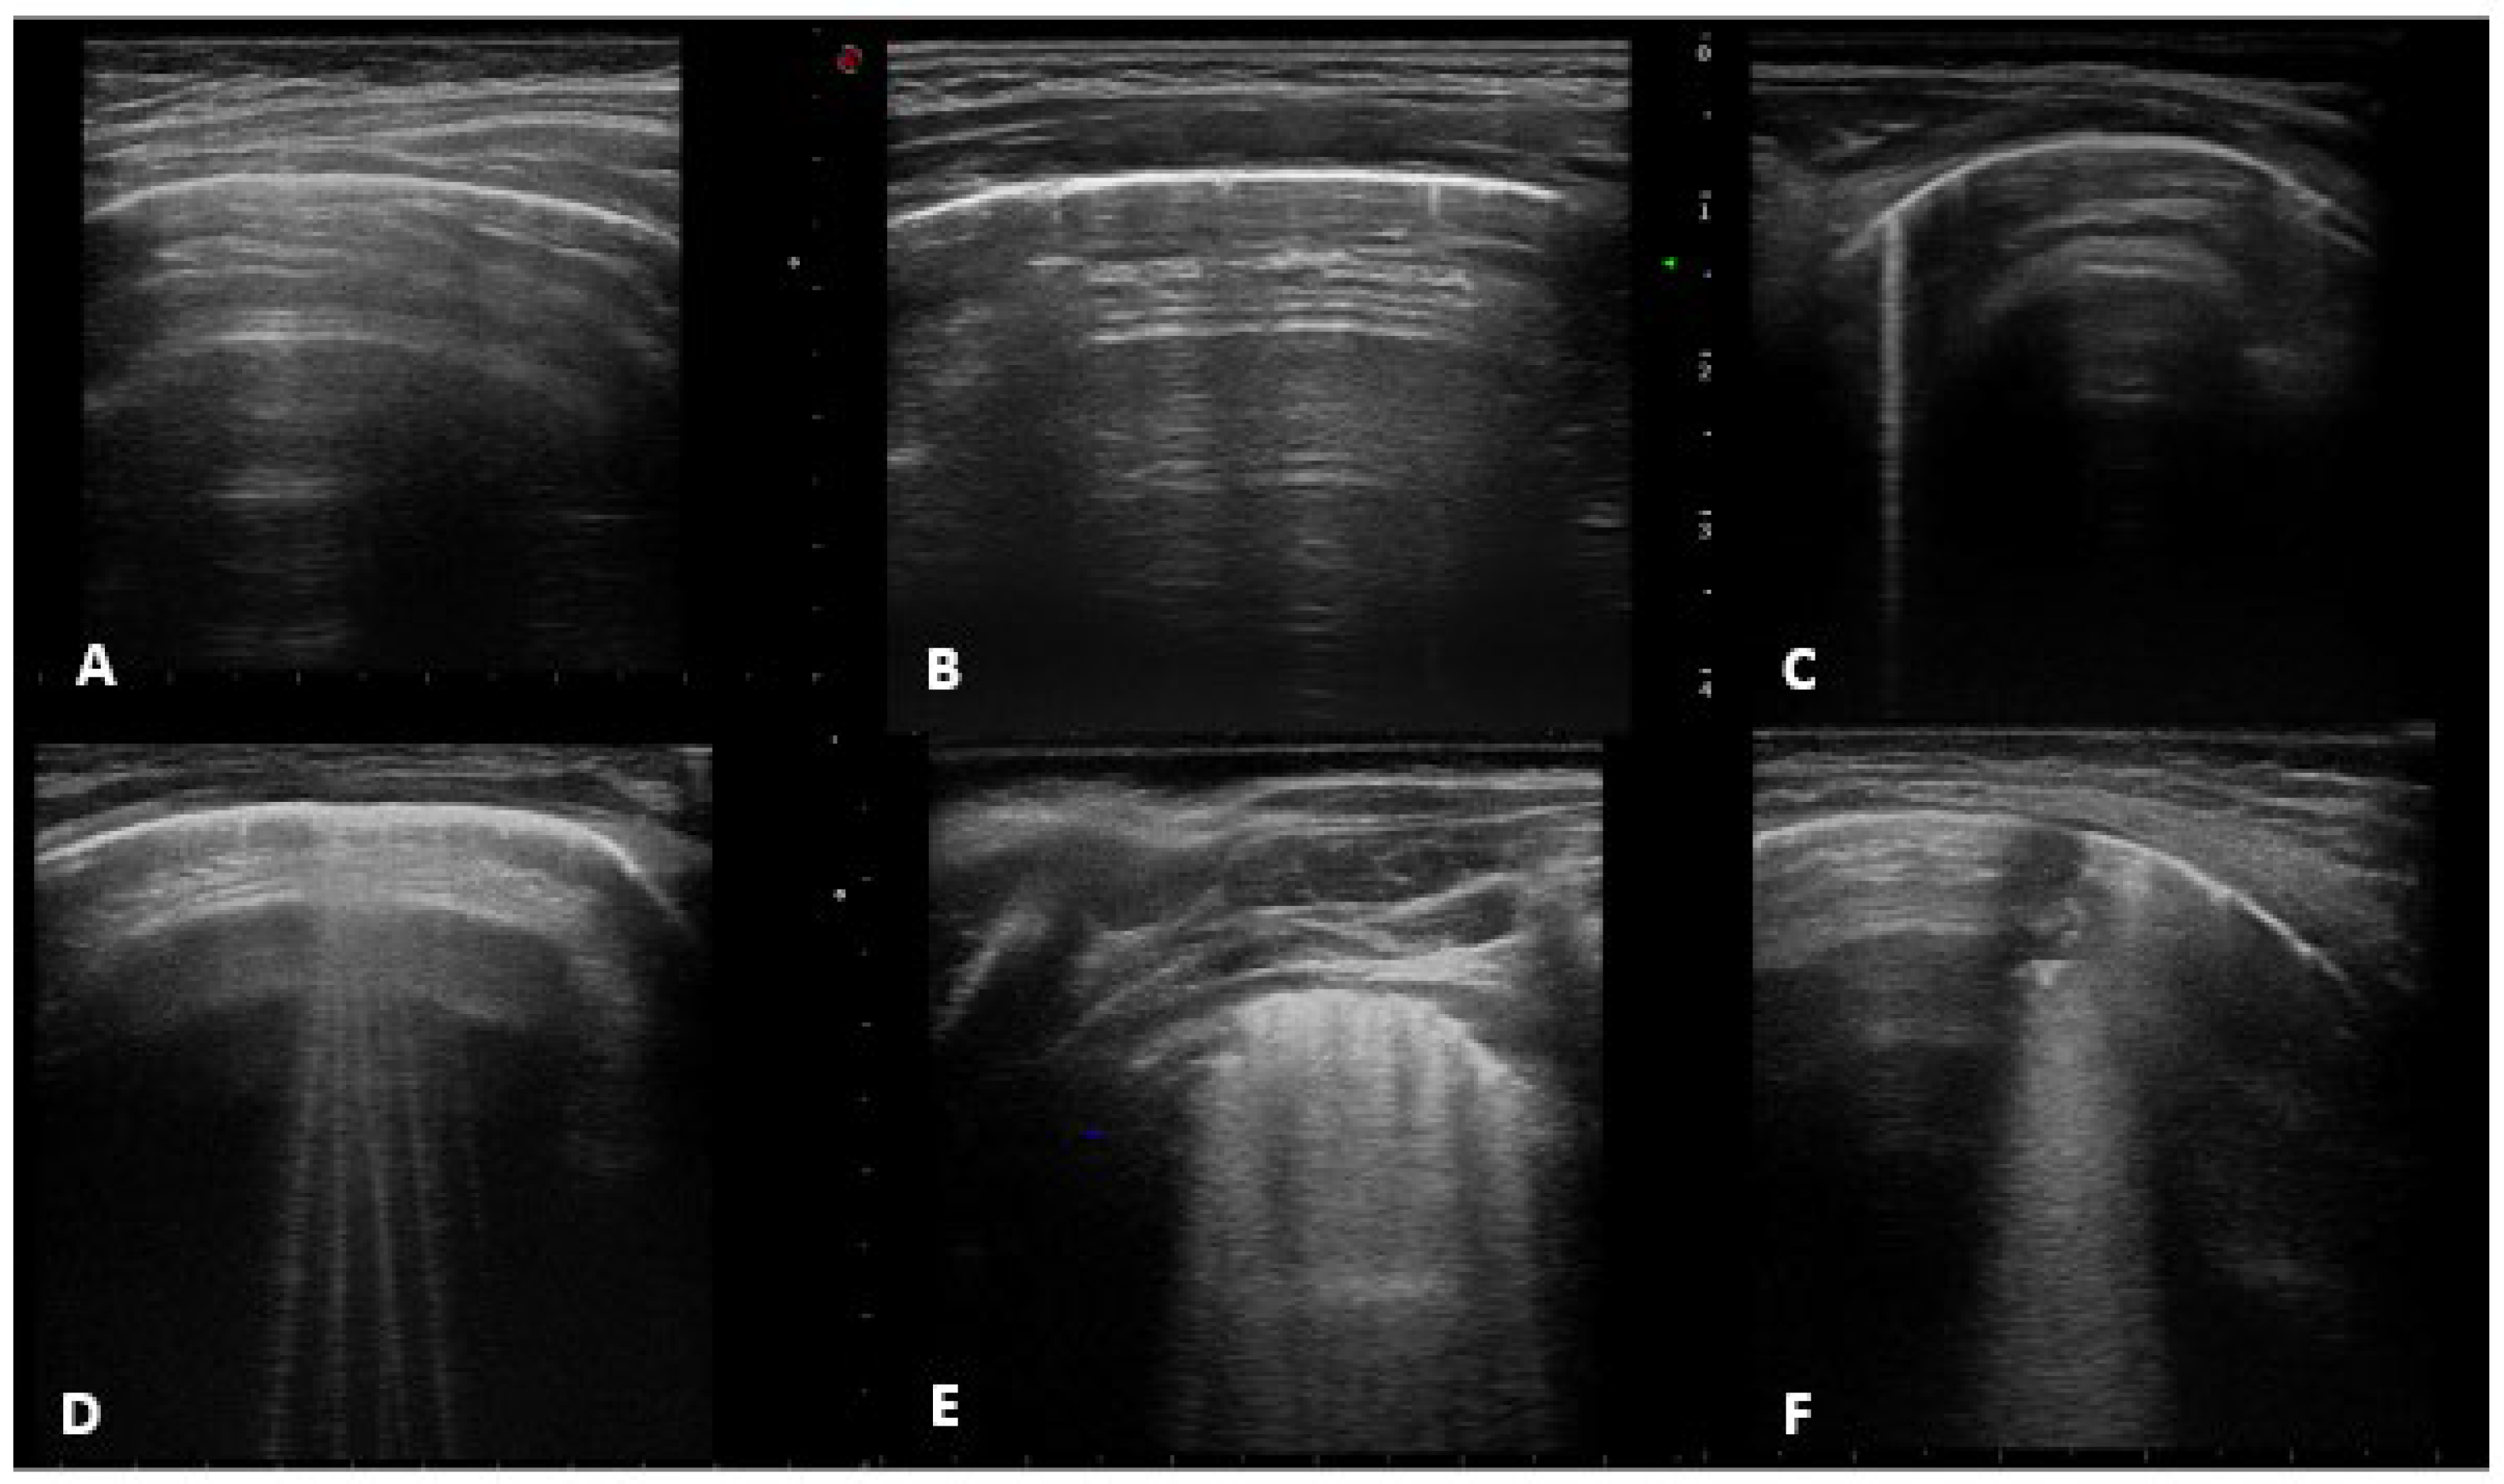

- Horizontal artifacts (the summation of the reverberation effects, due to the pleural-line and myofascial acoustic interfaces of the chest wall, and the mirror effects variable in its expression in relation to the thickness of the chest wall-reproducing beyond the pleural line, in a specular way, the myofascial planes of the chest wall) [25].

- Short vertical artifact (artifact that do not reach the bottom of the screen).

- B-line (hyperechogenic ultrasonographic artefacts, perpendicular to the pleural line, also known as comet-tail artefacts) that can be isolated (not more than 2 B-lines per intercostal space) or multiple (B-lines with a distance between them of less than half a cm to the confluence, remaining identifiable from each other).

- White lung (characterized by a granular and mostly white texture, which starts at the pleura line and ends at the bottom of the screen as reported in previously mentioned [25]).

- Sub-pleural consolidation (Subpleural echo-poor region interrupting the pleural line).

- A-lines, normal ultrasound with score 0.

- Short vertical artifact and Isolated-B lines with score 1 (counted together according to available literature See: https://doi.org/10.3390/app10051570, accessed on 24 July 2022).

- Multiple B-lines with score 2.

- White lung and subpleural consolidation less than 1 cm in size with score 3.

- Sub-pleural consolidation greater than 1 cm in size, score 4.